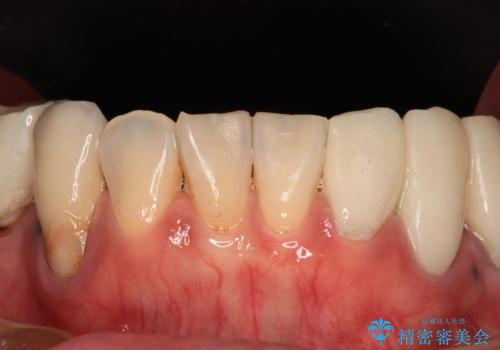

骨格的に下顎骨が前方位に位置しており、上下前歯部の先端同士が接触する切端咬合でした。

仮歯で咬み合わせの調整を行ってからは、特に不安定になることもなく、非常にスムーズに治療を進めて行くことができました。

前歯奥歯ともに望ましくない力がかかりやすい咬み合わせであるため、就寝時にはマウスピースを使用するようにお伝えしております。